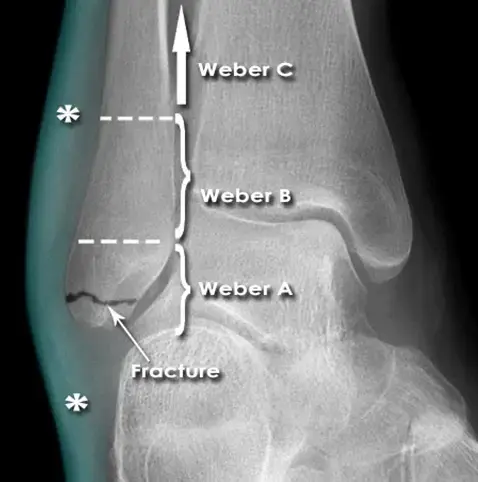

• الأشعة السينية الرقمية (Digital X-ray): لتقييم بنية العظام والمفاصل.